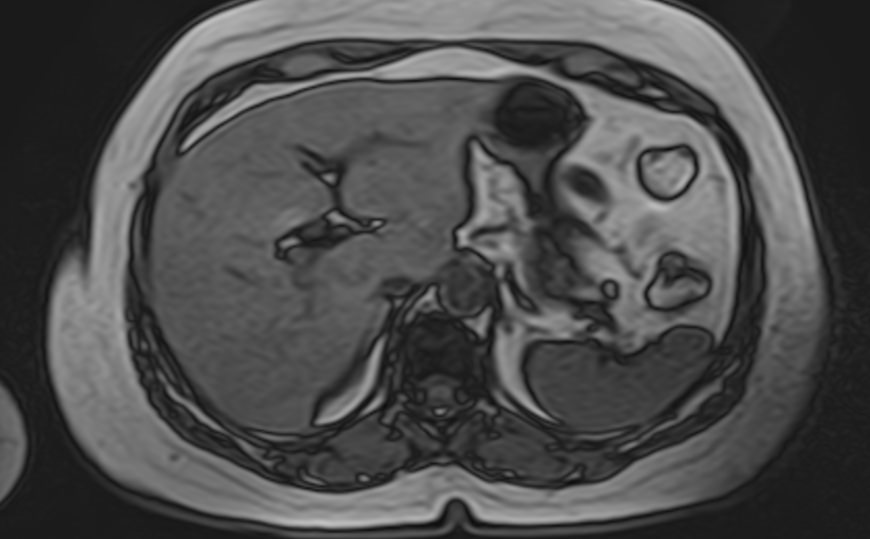

Магнитно-резонансная томография селезенки – высокоинформативный метод исследования органа с использованием внешнего магнитного поля, который позволяет с высокой точностью и достоверностью оценить структуру органа, его размеры, расположение, состояние сосудистой системы и паренхимы селезенки, а также окружающих тканей. МРТ селезенки часто применяется при гематологических заболеваниях, в онкологии, иммунологии.

МРТ селезенки: что показывает

• Новообразования (гемангиомы, саркомы и др.) и метастазы

• Повреждения селезенки (гематомы)

• Сосудистые нарушения (инфаркт, тромбоз вены селезенки, аневризма селезеночной артерии)

• Увеличение селезенки (при портальной гипертензии, болезни Гаучера и т.д.)

• Воспалительные процессы (абсцессы, саркоидоз, гистоплазмоз и др.)

• Кисты селезенки

• Признаки гематологических заболеваний

• Аномалии развития (добавочная селезенка и т.д.)